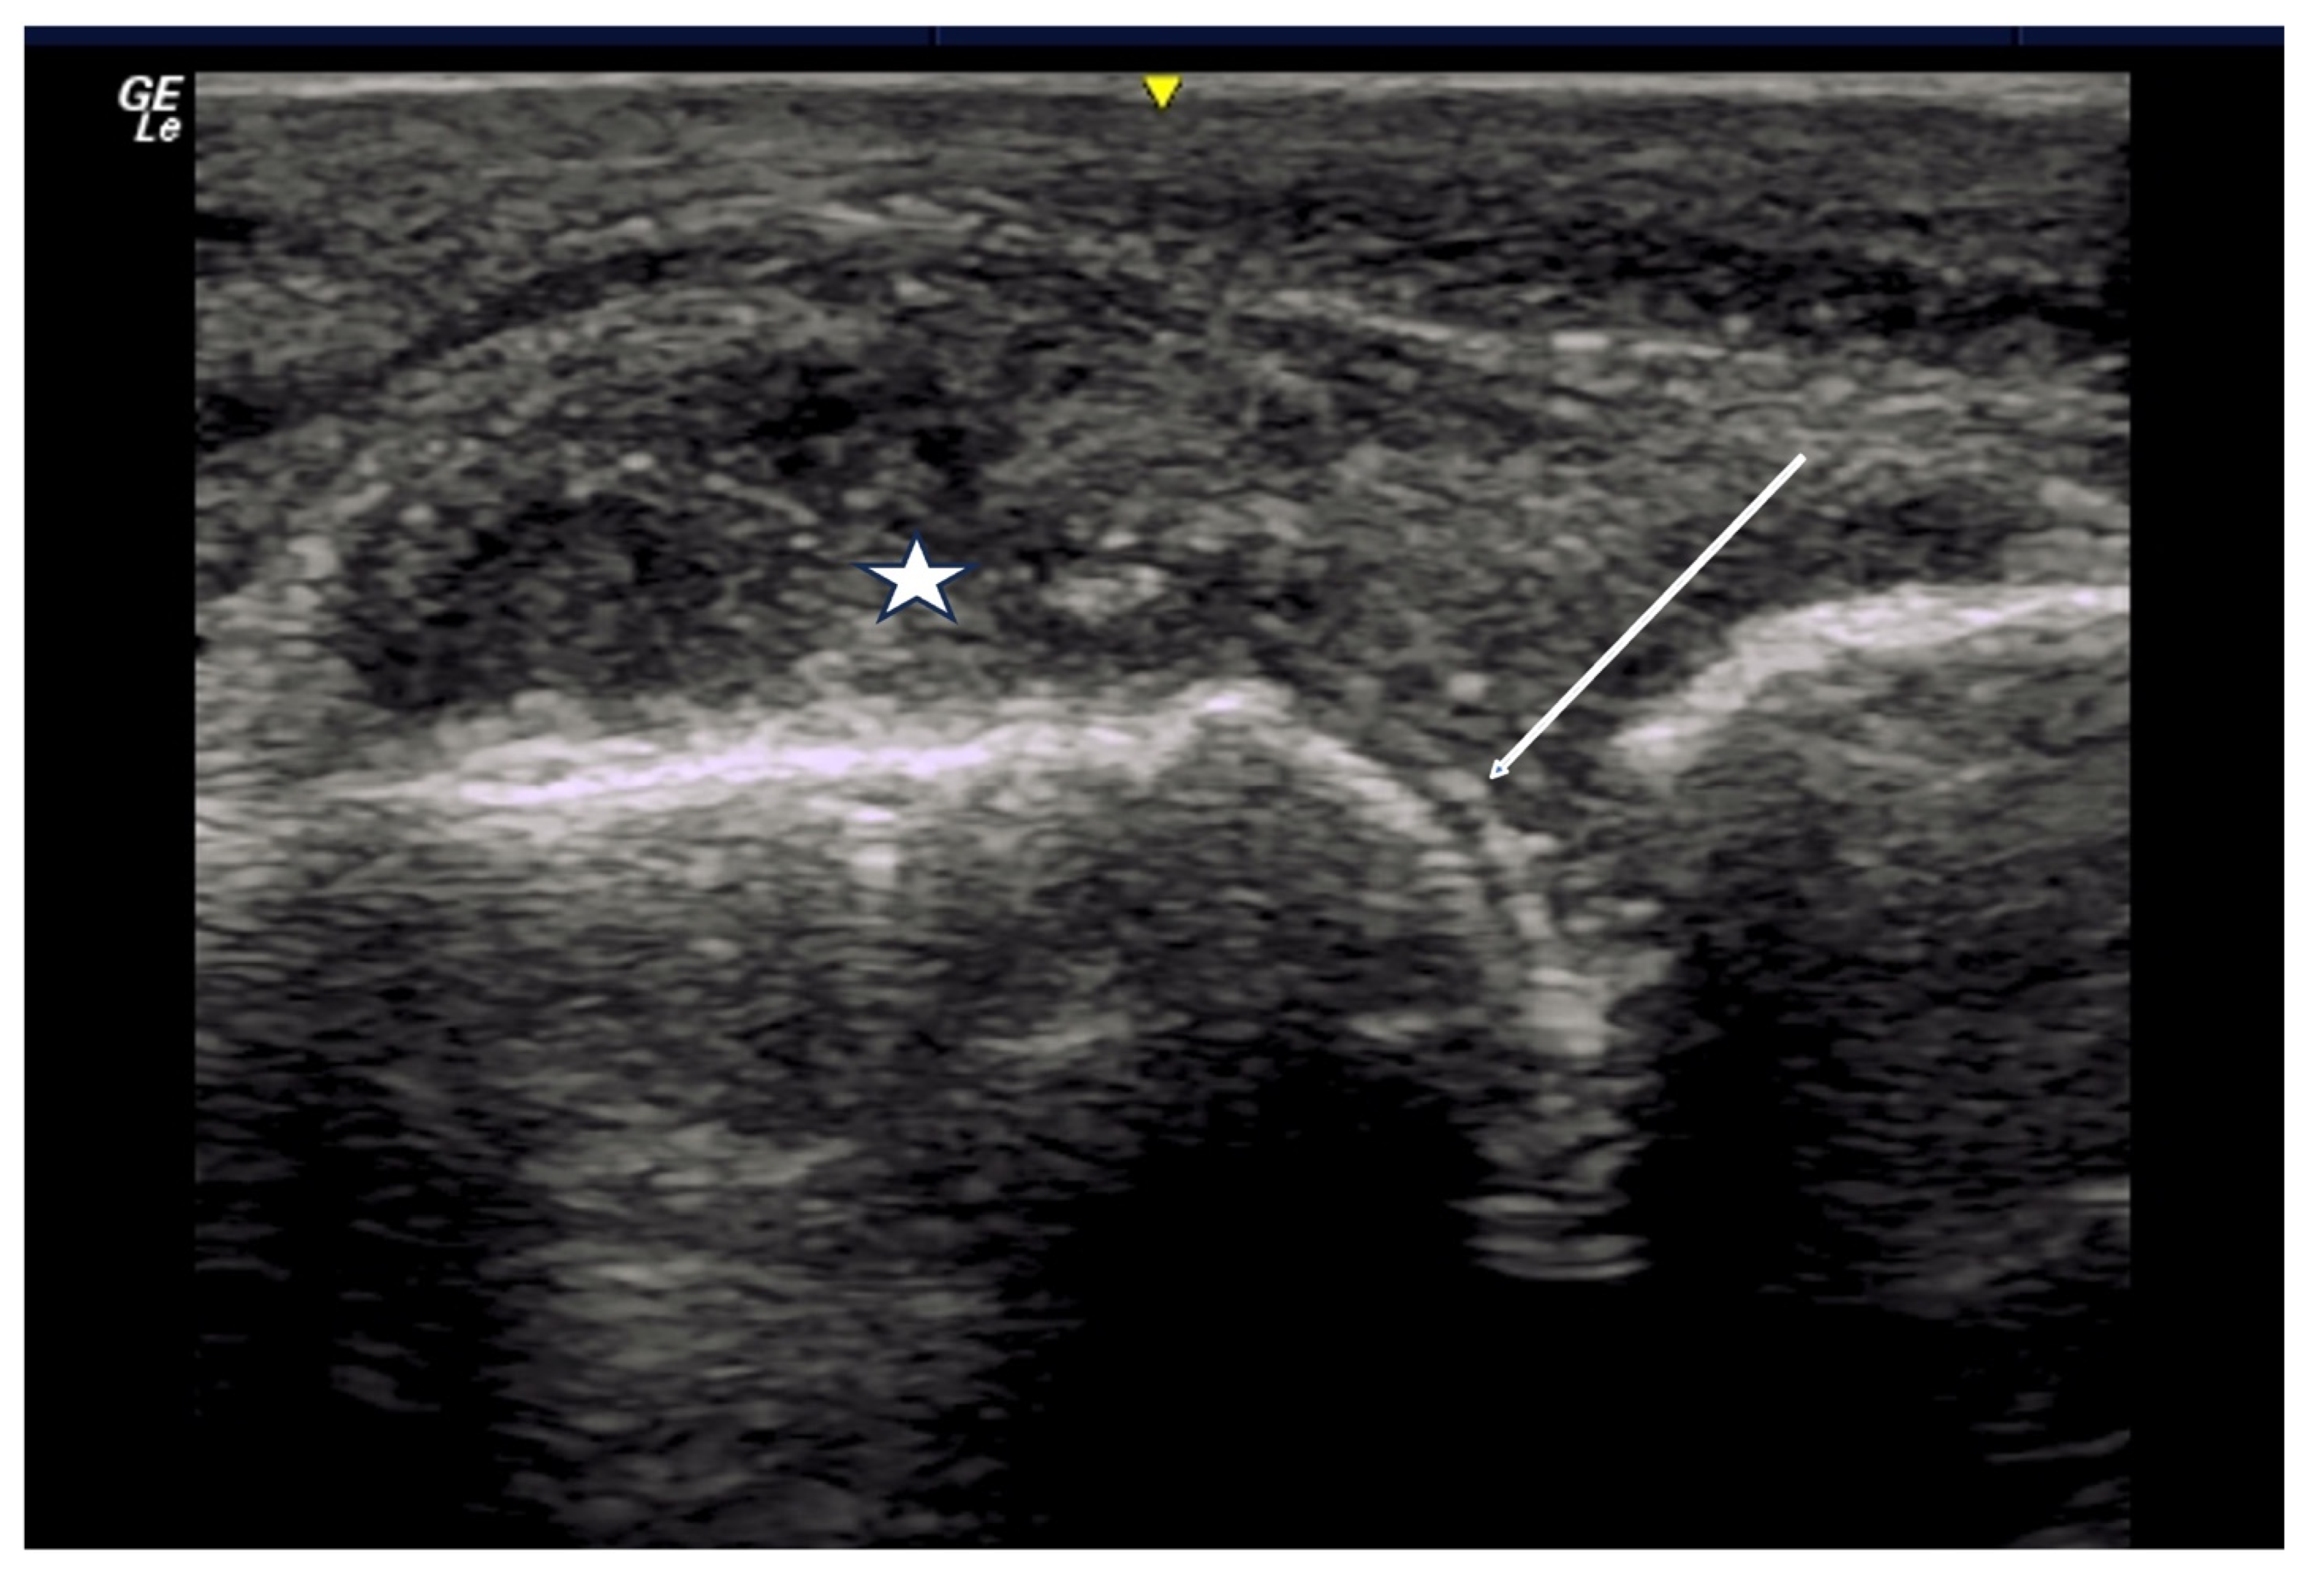

2.6. Calcium Deposition

3. Materials and Equipment